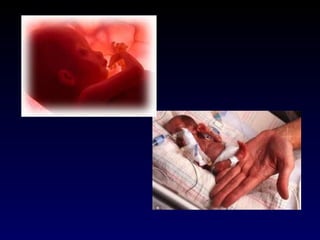

Período Fetal 9ª semana ao Nascimento   Caracteriza-se por rápido crescimento corporal e pela diferenciação dos sistemas

Período Fetal 9ª semana até o nascimento

As alterações que ocorrem no período fetal não são tão dramáticas quanto as que se dão na fase embrionária, mas são muito importantes.  O feto é menos vulnerável aos efeitos teratogênicos de drogas, vírus e radiação, mas estes fatores podem interferir com o desenvolvimento funcional normal, sobretudo do cérebro e dos olhos.

VIABILIDADE Capacidade razoável de manter uma sobrevivência fora do útero, com ou sem sustentação artificial. ~20 semanas ou 400 a 500gramas – imaturidade pulmonar!